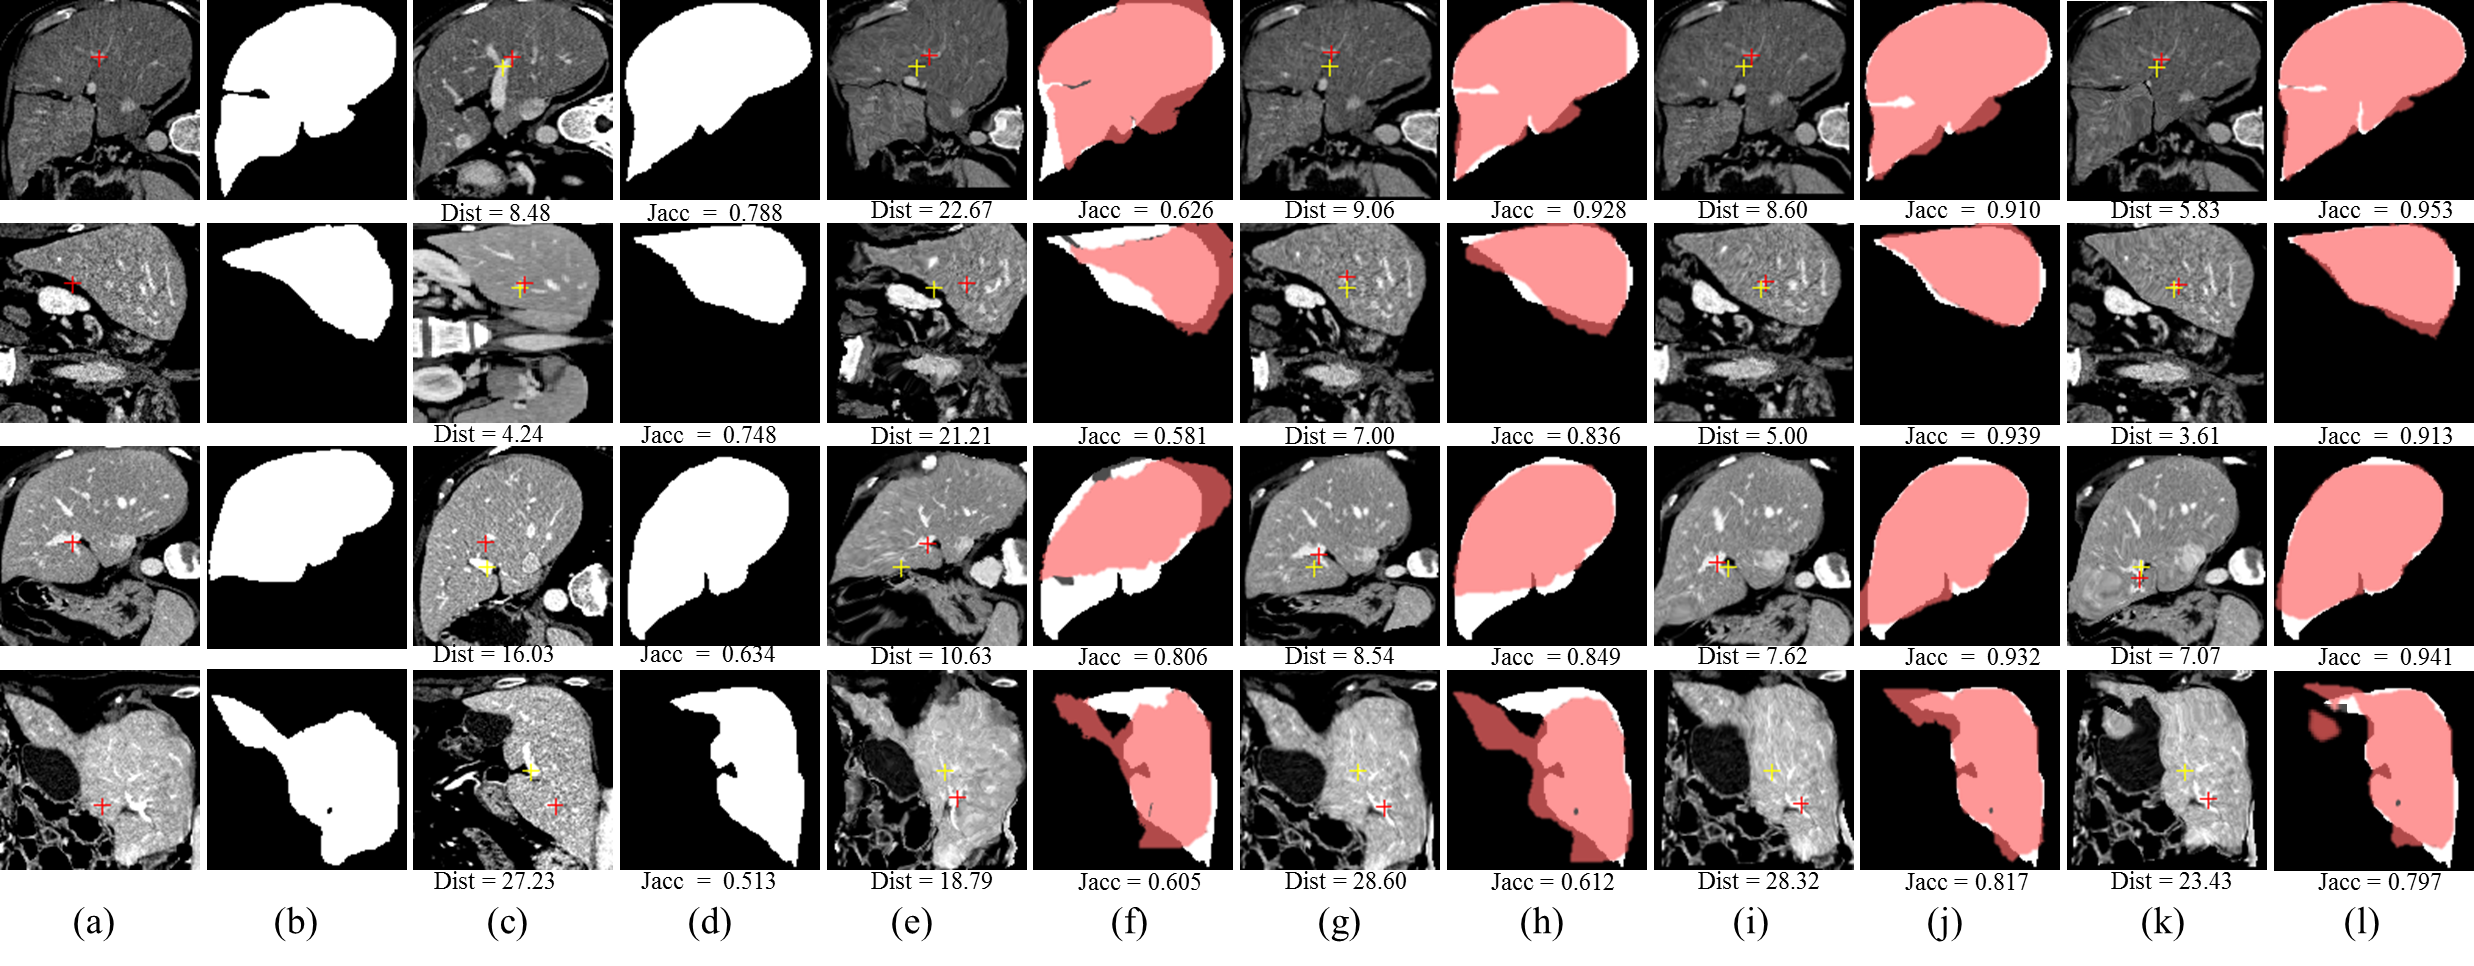

Refer to caption

Figure 5: Illustration of the brain registration performance of the proposed unsupervised methods, our best supervised baseline methods and the best traditional registration algorithms (itk16) with the best Dist: (a) Moving image, (b) Ground truth segmentation mask of moving image, (c) Fixed image, (d) Ground truth segmentation mask of fixed image. (e), (g), (i) respectively denote the moving images warped by the best traditional registration algorithm (itk16), our best supervised baseline method (itk16), our best unsupervised method (PE). The translucent red masks in (f), (h) and (j) respectively correspond to (e), (g), (i) and denote the warped ground truth segmentation mask of the moving images. The white masks in (f), (h), (j) are the ground-truth segmentation mask of the fixed image. The red and yellow crosses denote landmarks of moving image and fixed image, respectively. Dist in (c) and Jacc in (d) denote no registration.

Table I quantitatively shows the performance of our unsupervised methods, our best baseline (supervised methods) and the best traditional registration algorithms. Jaccard Coefficient (Jacc) and Distance Between Corresponding Landmarks (Dist) are used as evaluation metrics. The running time (Rt) for each algorithm to register a pair of images is reported. The unsupervised methods PN and PE are 100x faster than traditional methods while achieving superior registration performance (Dist and Jacc). Besides, the unsupervised methods are superior to supervised methods. Figure 5 illustrates the registration results of different methods.